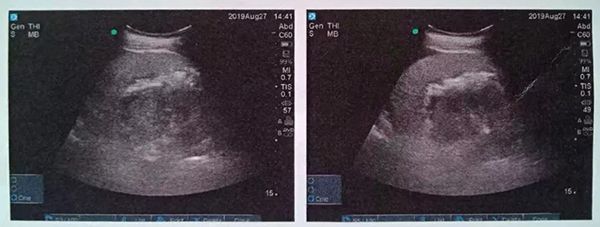

術(shù)中,泌尿外科郭駿博士精心設(shè)計手術(shù)通道,只在患者體表鉆出兩個0.5厘米的小洞,由于患者右側(cè)上位腎位置高,靠近肝臟和肺下葉,容易出現(xiàn)肝臟和肺的損傷,在B超的引導下精確穿刺腎結(jié)石的最高點,逐級擴張后建立皮腎通道。這時屢次“惹禍”的腎結(jié)石清楚的顯露在手術(shù)屏幕上,結(jié)石呈淺黃色,表面覆蓋淺褐色的膿苔,然后使用鈥激光將結(jié)石擊碎后取出。歷時一個半小時,結(jié)石全部清除,手術(shù)結(jié)束。

這種方式是在超聲實時引導下,在腰部經(jīng)皮膚穿刺建立通道(俗稱打洞)進入腎臟,找到腎結(jié)石后用鈥激光碎石。